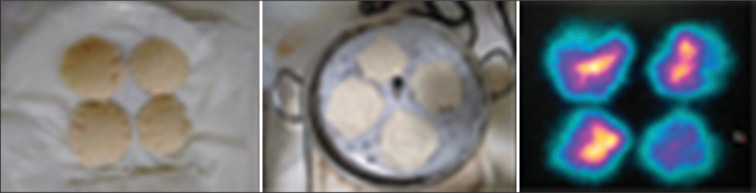

Materials and methods: Following various types of solid meal preparations were labeled with 3 mCi of 99 mTc sulfur colloid (SC), and image of each meal was acquired on General Electric (GE) Infinia Hawkeye 4 camera: (1) Meal of 4 slice bread + 20 g butter with calorific value ≈ 356 kcal. (2) 4 slice bread + 30 g jam with calorific value ≈ 332 kcal. (3) 4 slice bread + 70 ml of milk with calorific value ≈ 243 kcal. (4) 150 g of sagu (sabudana) +5 ml refined vegetable oil + 10 g peanuts (sagu khichdi) with calorific value ≈ 324 kcal. (5) 4 idli + 2 tablespoon green chutney with calorific value ≈ 280 kcal. (6) 70 g wheat + 50 ml water + 5 ml refined vegetable oil with calorific value ≈ 237 kcal. (7) Meal of 75 g of idli mix + 80 ml water + 10 g butter with calorific value ≈ 310 kcal. All radiolabeled meals were subjected to the radiolabeled stability test procedure to calculate labeling efficiency which was compared.

Results: Idli meal prepared with radiotracer added to the batter mixture itself, with a calorific value ≈ 310 kcal showed the highest uniform Tc99 m SC distribution in comparison to all other meal preparations.

Conclusions: Radiolabeled idli (savory cake) prepared with radiotracer added to the batter mixture itself, appears to be an ideal vegetarian meal in comparison to all other meal preparations for gastric emptying scintigraphy studies, especially among patients with specific dietary restrictions.